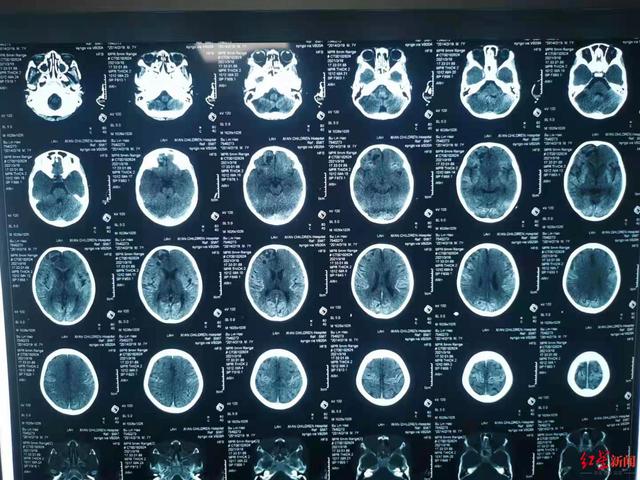

小军的脑部CT光片及西安市儿童医院3月18日出具的相关报告 。 受访人供图